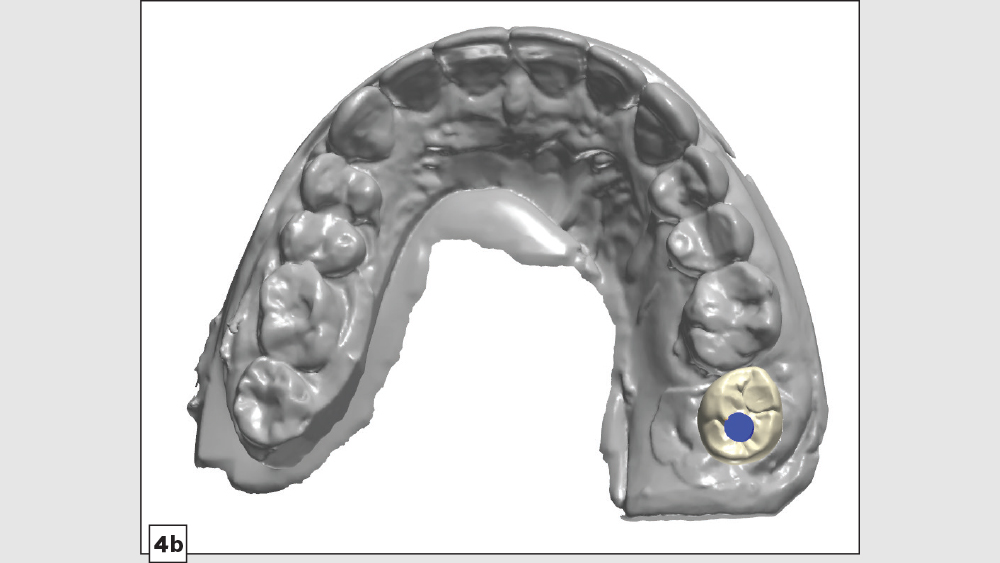

Now that we’ve explored the pros and cons of screw-retained and cementable implant restorations, let’s take a look at a unique clinical situation where the best solution is a hybrid of the two. With a “screwmentable” solution, a custom abutment is designed to support a cementable restoration, but the crown is created with a screw access hole. The cementation portion of restoration delivery — as well as cleanup of any excess cement — is performed outside of the patient’s mouth. This creates what is essentially a one-piece restoration that avoids any concerns regarding retained cement at the implant site, with greater control over the design of the emergence profile.

A patient presented with issues concerning a screw-retained crown in the area of tooth #15. She complained that the crown felt loose, was causing food entrapment and was difficult to clean. Upon examination, it appeared that the prosthetic screw was loose and the restoration was mobile. Removal of the crown confirmed that the current design of the prosthesis created a food trap and was not conducive to soft-tissue health. We agreed that the restoration needed to be replaced. A screwmentable restoration was the optimal solution because the malposition of the implant could be corrected by a custom abutment, thereby minimizing the cantilever. We wanted to improve the direction of loading and lessen sheer forces on the implant site by building the restoration out with the titanium structure of the custom abutment. At the same time, because the implant site was in a hard-to-reach area from which cement removal would have been difficult, screw retention was preferred.